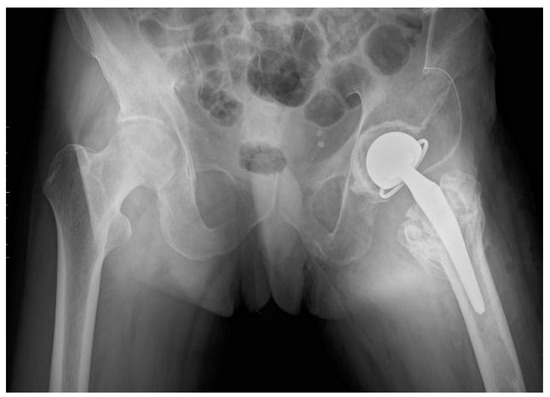

| First Stage of Treatment—January 2023 Removal of the failed fixation, filing the bone defects with calcium sulphate antibiotic carrier | ||